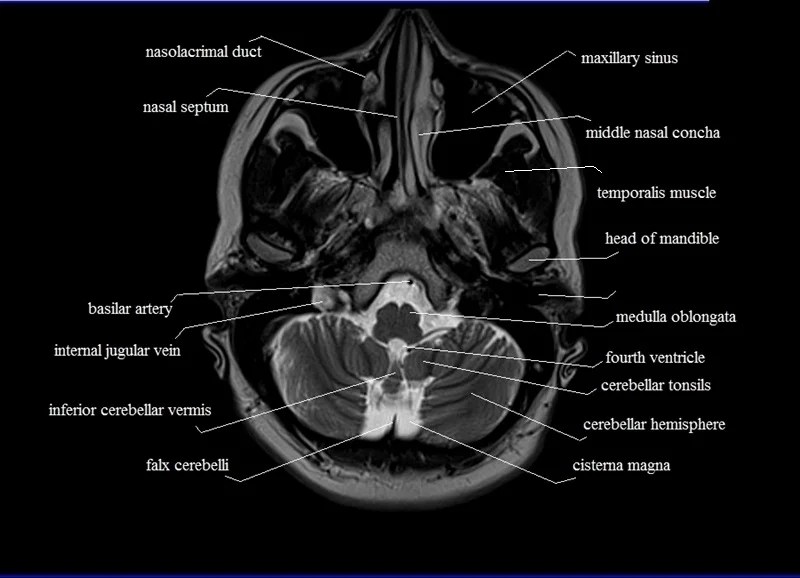

MRI anatomy Free MRI Axial Brain Anatomy Mri Anatomy Axial Note, however, that mcrae’s line (basion. A brain mri is one of the most commonly performed techniques of medical imaging. The anatomy of the brain is studied by means of axial, coronal and sagittal views. Mri axial cross sectional anatomy of brain. The mri sequence used is a 3d gradient. It is the most complete reference of human anatomy available.. Mri Anatomy Axial.